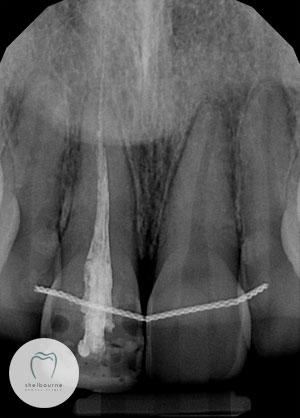

Digital x-ray of Mary’s front teeth showing the root canal treatment

Here is the x-ray which I took when Mary came into us that first morning.

Check out my x-ray with the flashing dots on it. I’ve placed red dots to show where the tip of the root is. We like to fill the root canal to this tip or just short of it. The blue arrows show where some root canal filling material is squashed out way beyond the tip of the root and into the surrounding bone.

Root Canal material extruded

Sometimes this filling may go out beyond the root tip and never cause problems. Here however, the material is well beyond the tip and is undoubtedly the cause of Mary’s discomfort.